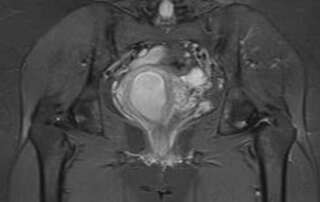

Haematometra following a caesarean section: a rare and avoidable complication

DOI: 10.36205/ trocar3.2022005